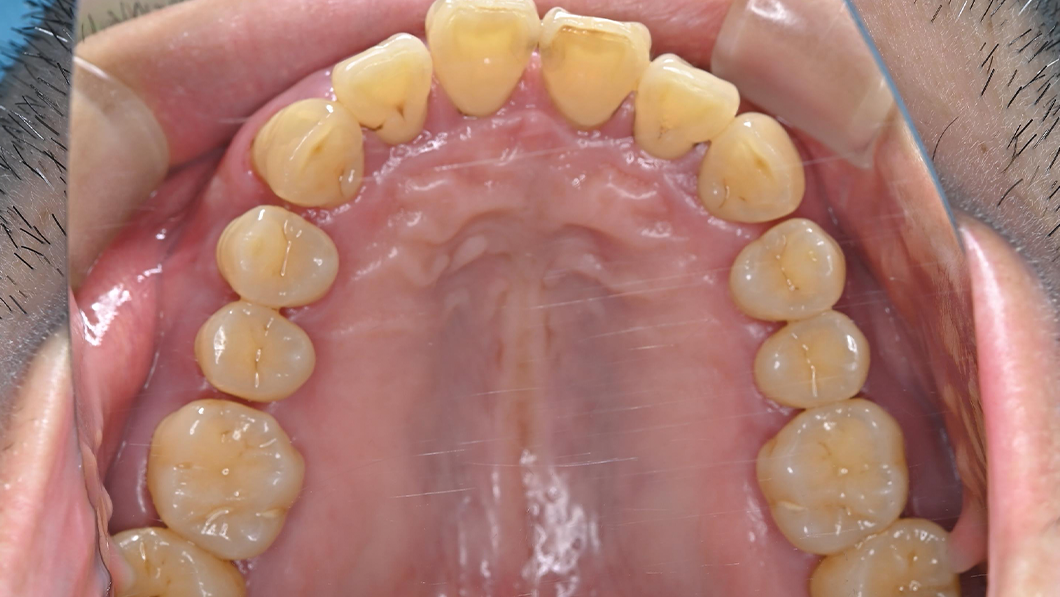

【40代 男性】歯周基本治療

治療前

主訴 全額的歯周病による歯周組織の炎症

治療内容 SC、SRP、歯科衛生士実地指導、TCH指導